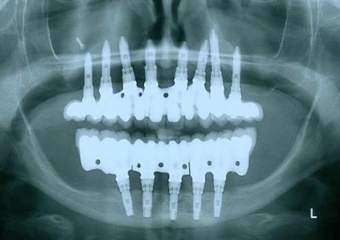

Raio X final, com as próteses em porcelana já instaladas - Clínica Cliniface

Raio X final, com as próteses em porcelana já instaladas